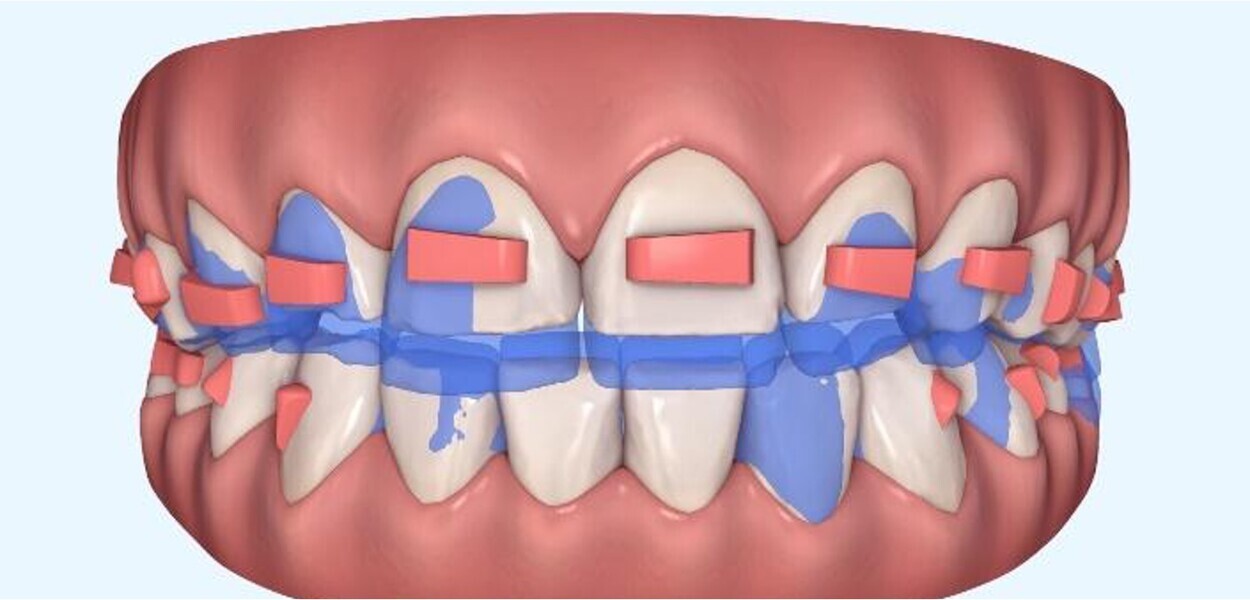

Fig. 4: Orthodontic digital simulation using Invisalign software to show the pretreatment position (blue) and the predicted result after treatment (white).

This patient desired improvement of her smile aesthetics with minimal restorative involvement (Figs. 2–4). She presented with significant excess gingival display in the maxilla, producing a gummy smile from tooth #15 to tooth #25 of about 5 mm. The patient also had a maxillary midline towards the left side and a thin upper lip. The patient had a dental Class II/I relationship on the left side and healthy gingival tissue of a medium-thickness biotype with no signs of local or general gingivitis or periodontitis. There were also no signs of any restorations or risk of or active dental caries.